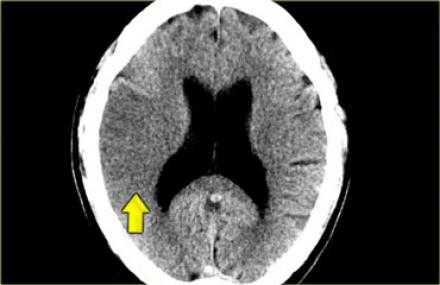

- — Симптом плотной СМА.

Симптом плотной СМА.

Данный симптом проявляется в следствии тромбирования или эмболизации СМА. У ниже представленного пациента симптом плотной СМА. На КТ ангиография визуализируется окклюзия СМА.